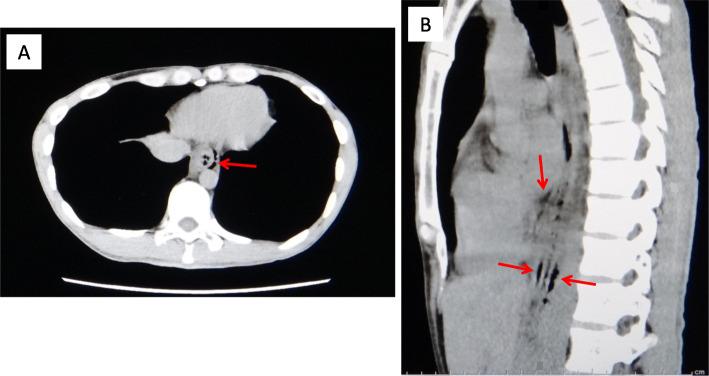

The patient in case 1 complained of severe chest pain and nausea and vomited on arrival at the hospital. He was subsequently diagnosed with Boerhaave syndrome coupled with mediastinitis using computed tomography (CT) and esophagogram. An emergency operation was successfully performed, in which a 3-cm tear was found on the left posterior wall of the distal esophagus. The patient subsequently had anastomotic leakage but was discharged 41 days later. The patient in case 2 complained of severe chest pain, nausea, vomiting, and hematemesis on arrival. He was suggested of having Boerhaave syndrome without mediastinitis on CT. The symptoms gradually disappeared after conservative treatment. Upper gastrointestinal endoscopy performed on the ninth day revealed a scar on the left wall of the distal esophagus. The patient was discharged 11 days later. In addition to the varying severity between the cases, the patient in case 2 was initially considered to have Mallory-Weiss syndrome.

病例1中的患者在入院时主诉严重胸痛、恶心并呕吐。随后通过计算机断层扫描(CT)和食管造影被诊断为Boerhaave综合征合并纵隔炎。成功进行了急诊手术,术中发现食管远端后壁有一处3厘米的撕裂口。该患者随后出现吻合口漏,但在41天后出院。病例2中的患者在入院时主诉严重胸痛、恶心、呕吐和呕血。CT检查提示其患有Boerhaave综合征但无纵隔炎。保守治疗后症状逐渐消失。在第9天进行的上消化道内镜检查显示食管远端左壁有一处瘢痕。该患者在11天后出院。除了病例之间严重程度不同外,病例2中的患者最初被认为患有马洛里-魏斯综合征。